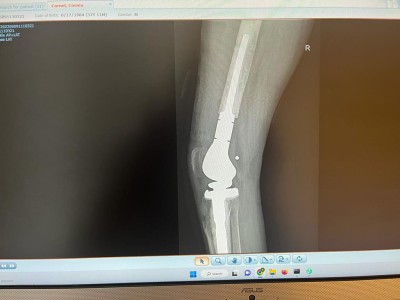

ORTOPEDIE-TRAUMATOLOGIE: Interventie chirurgicala de protezare segmentara a genunchiului la un pacient tanar cu fractura deschisa la nivelul genunchiului

"Defectul osos mare de la nivelul femurului distal impun o reconstructie a genunchiului cu endoproteza segmentara pentru defect femural mare pe care impreuna cu echipa mea (dr. COSTE REMUS, dr. DRAGHICIOIU HOREA, dr. MUBARAK FADOL, as. GAVRA MONICA) am efectuat-o in luna iunie 2022. Lipsa mare de os de la nivelul femurului distal am inlocuit-o cu un sistem GMRS Stryker.

Postoperator, pacientul a fost preluat de echipa de fizioterapeuti, redoarea genunchiului fiind foarte avansata. Retractia marcata a partilor moi permit o flexie de maxim 30 grade, aceasta crescand progresiv cu ajutorul colegilor din departamentul de Recuperare, dar si cu vointa si perseverenta puternica a pacientului.

La 6 luni postoperator pacientul are un mers normal, alearga usor si desfasoara activitati sportive usoare".